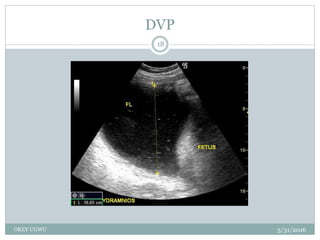

DVP

5/31/2016OKEY UGWU